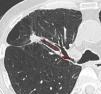

DY and VY depended on the size of the lesion, being 64.0% and 80.0%, respectively, for PPL≤20mm (n=25), and 80.8% and 84.6%, respectively, for PPL>20mm (n=26). Regarding other radiologic nodule characteristics including PPL-pleura distance, the VY significantly improved (P=.021) only when the distance from the hilum (Fig. 2) was <50mm, while no radiologic predictor was identified for DY (Tables 2 and 3).

Some of the innate limitations of a retrospective analysis, such as possible selection bias favoring patients at high-risk for malignancy and bronchoscopically accessible PPL, cannot be excluded in this study. Nevertheless, the diagnostic yield reported here lie on the linear regression line between the prevalence of lung malignancy and R-EBUS sensitivity performed by Steinfort et al.18 Another limitation, inherent to most trials studying the diagnosis of PPL, concerns the establishment of diagnosis and the histocytological criteria used for malignancy. In our study, the combination of histopathological criteria and clinical follow-up in uncertain cases resulted in no false-positive cases. Finally, a new method based on oblique reformatted images was used to estimate the distance between the hilum and the PPL (Fig. 2). The study of Tay et al. introduced the Pythagoras formula for calculating the distance of the PPL from the hilum on a 3D perspective.24 However, with this method the real bronchial pathway distance is not taken into account. In this study, oblique reformatted images permitted the calculation of the distance between the most internal PPL margin and the origin of the segmental bronchus in question, giving a more accurate estimation of the bronchial pathway to be followed during the bronchoscopic intervention.